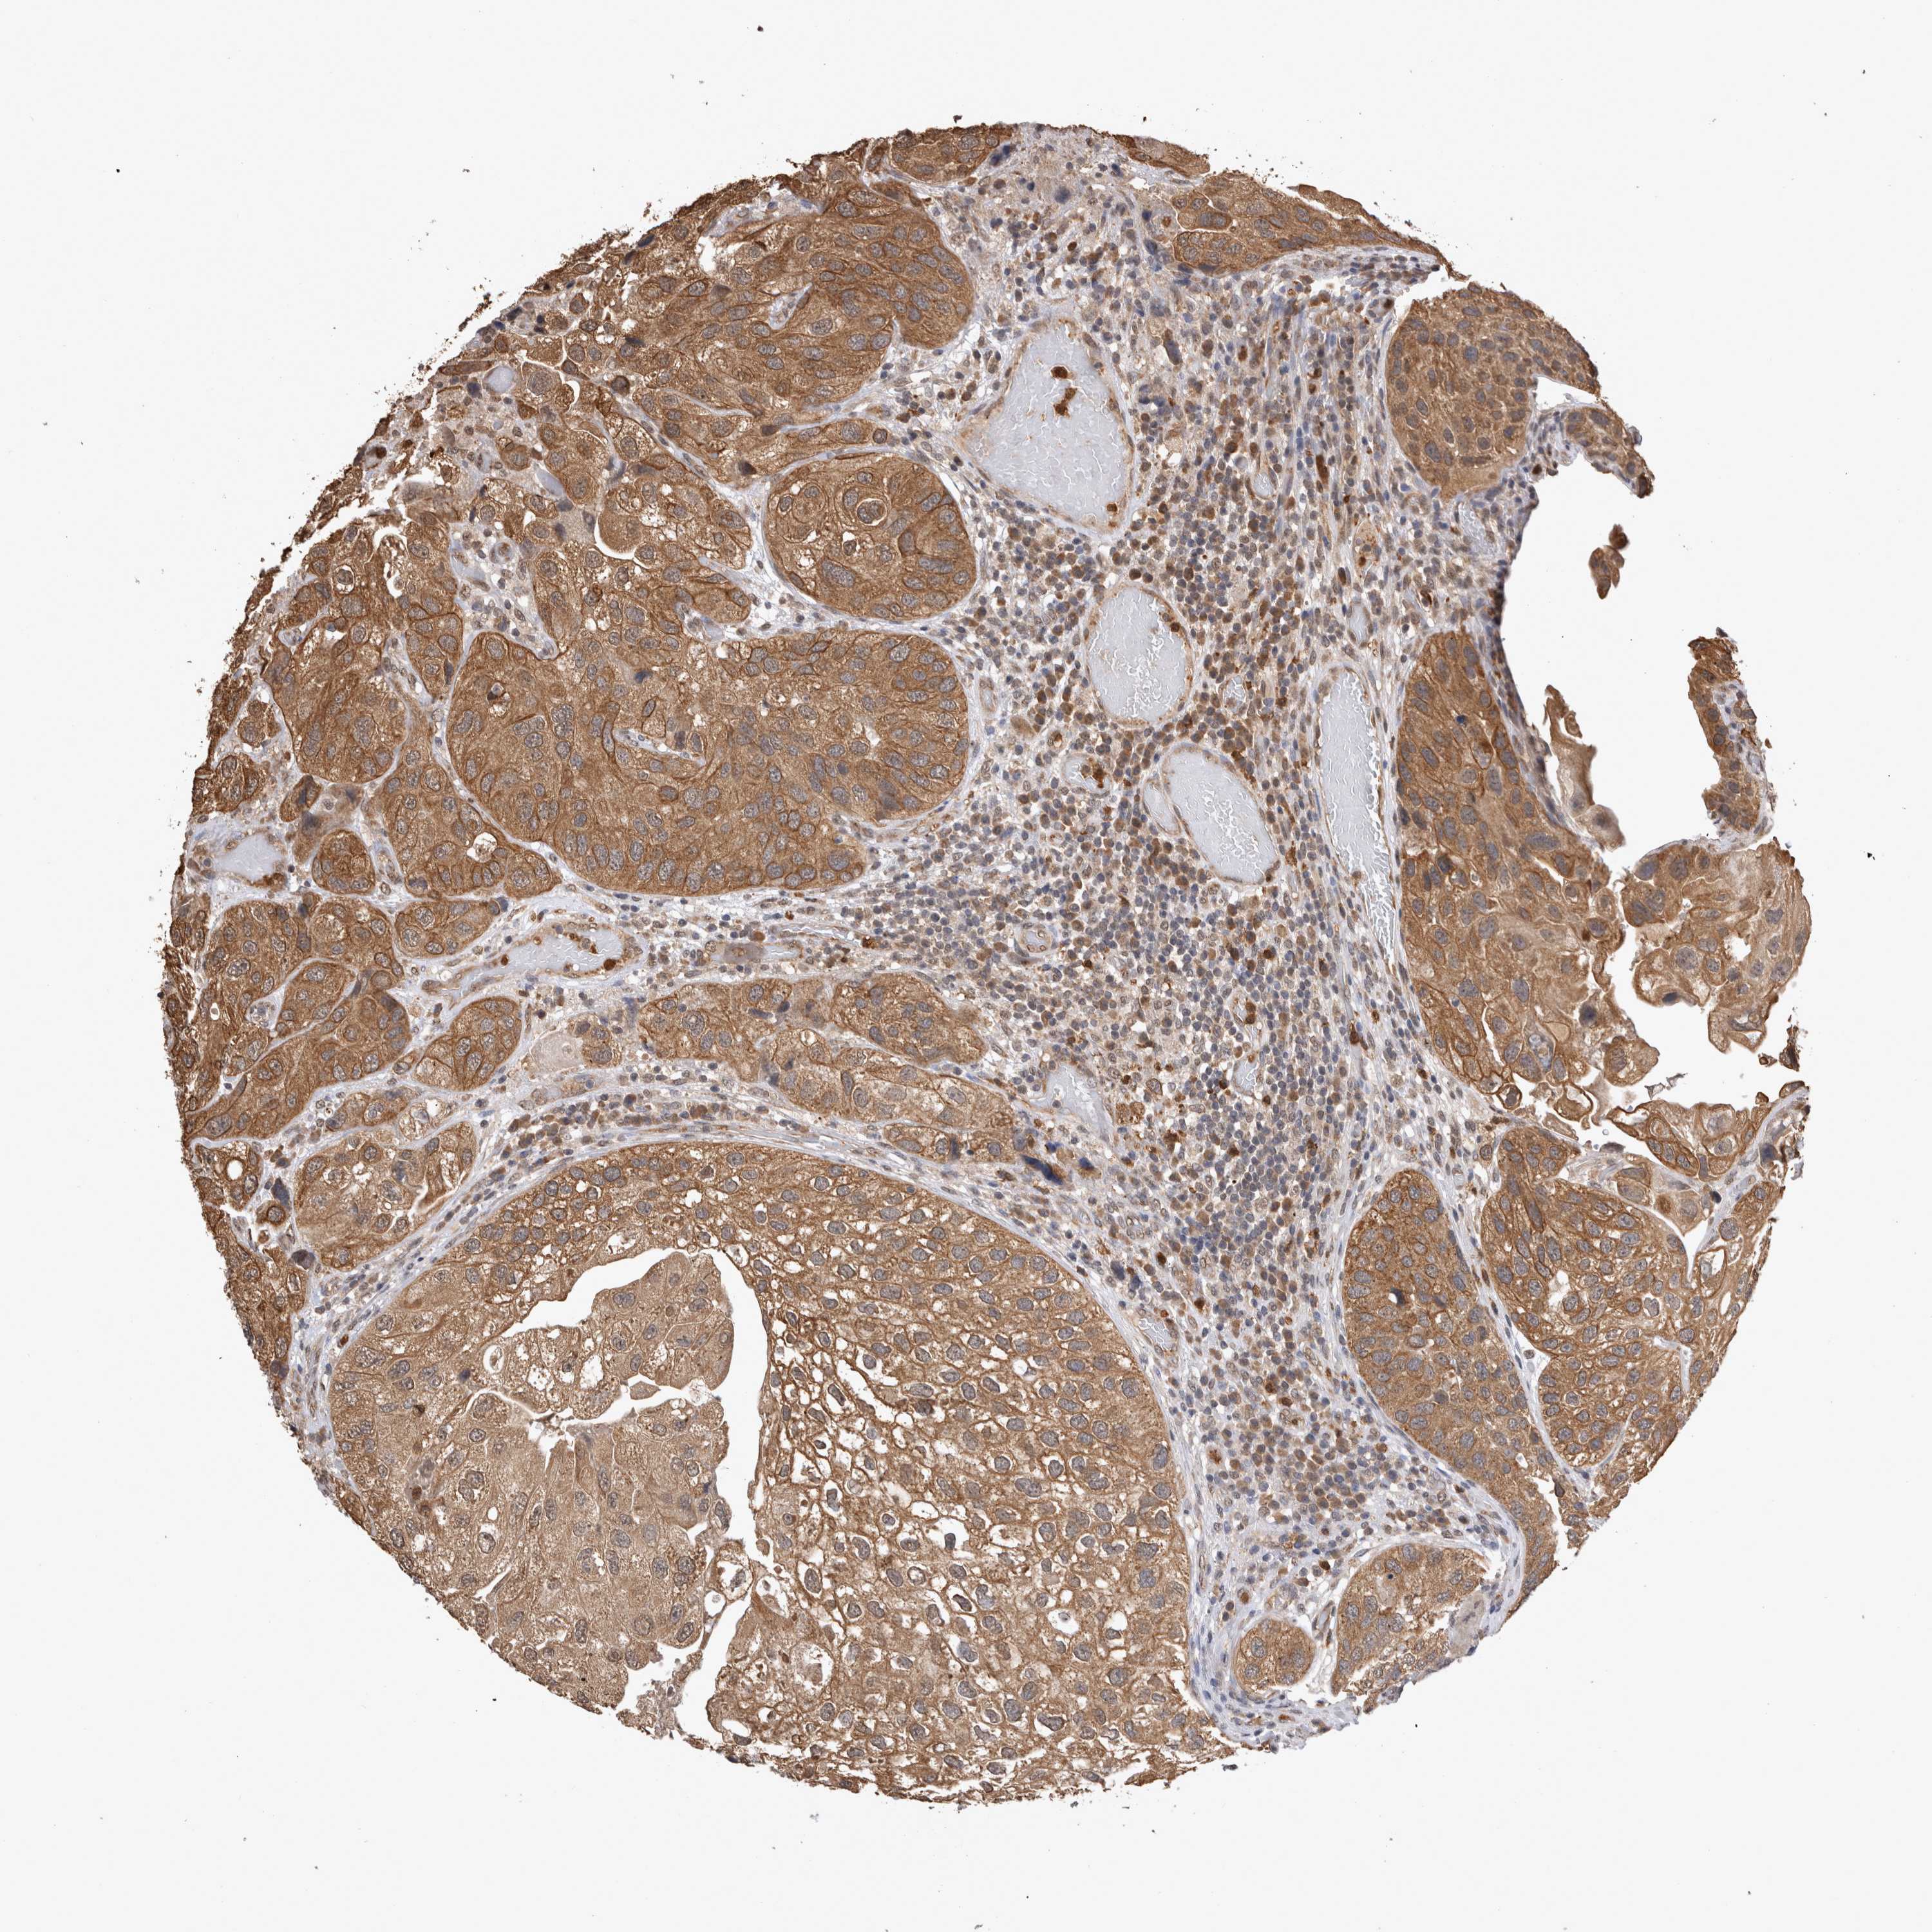

UROTHELIAL CANCER - Protein expressioni

A mouse-over function shows sample information and annotation data. Click on an image to view it in a full screen mode. Samples can be filtered based on level of antibody staining by selecting one or several of the following categories: high, medium, low and not detected. The assay and annotation is described here.

Note that samples used for immunohistochemistry by the Human Protein Atlas do not correspond to samples in the TCGA dataset.

Antibody stainingi

Antibody staining in the annotated cell types in the current human tissue is reported as not detected, low, medium, or high, based on conventional immunohistochemistry profiling in selected tissues. This score is based on the combination of the staining intensity and fraction of stained cells.

Each image is clickable and will lead to virtual microscopy that enables deeper exploration of all samples and also displays staining intensity scores, fraction scores and subcellular localization as well as patient and tissue information for each sample.

Antibody CAB025747

Antibody CAB044670

Staining

High

Medium

Low

Not detected

Intensity

Strong

Moderate

Weak

Negative

Quantity

>75%

75%-25%

<25%

None

Location

Nuclear

Cytoplasmic/membranous

Cytoplasmic/membranous,nuclear

Urothelial carcinoma, Low grade

Urothelial carcinoma, High grade